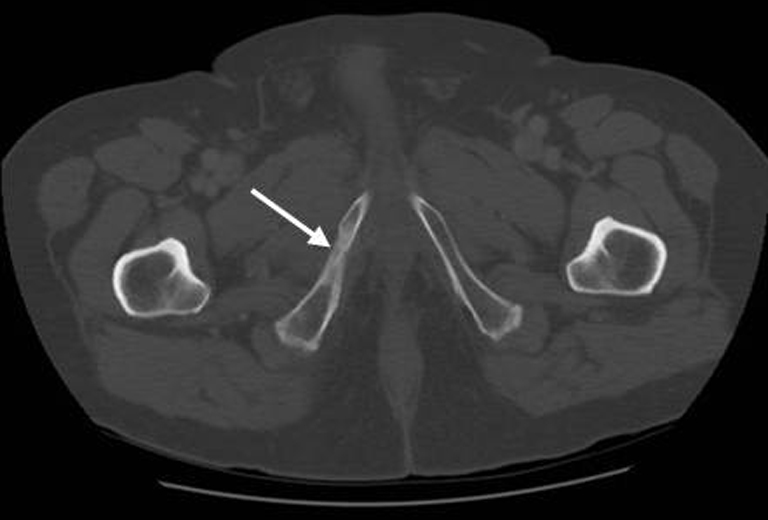

18+ Bone Mets Images. Bone metastases, or osseous metastatic disease, is a category of cancer metastases that results from primary tumor invasion to bone. Bone mets are potentially quite damaging.

Learn vocabulary, terms and more with flashcards, games and other study tools. Bone metastasis can cause pain and broken bones. This is called bone metastasis, or bone mets, and it's different from cancer that starts in the bone.

Bone mets are potentially quite damaging. Cancer that leads to bone metastasis may have started in your breast, your prostate, your lungs. Severe skeletal related events, such as fractures and spinal cord. Through how many mechanisms does bone mets spread, and what are they?